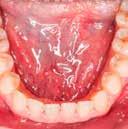

1. ábra: Nyelv helyzete az okkluzális sík felett.

2. ábra: Mallampati besorolás 4, mindegyik minimális orális térfogatot jelez.

angiotenzin II receptor antagonista) 50 mg naponta egyszer, Nexium (protonpumpa-gátló, amely csökkenti a gyomorban termelődő sav mennyiségét) (GERD) 40 mg naponta, Intuniv (multivitamin) 4 mg naponta, és aszpirin 81 mg naponta egyszer. Klinikailag a nyelv az okkluzális sík fölött helyezkedett el, hiperkeratózis (B), a nyelv légutakba való behúzódása és Mallampati 4, amely mind minimális szájüregi térfogatra utalt (1–2. ábra). Ezek indikálták az alvásfogászati készülékes kezelést. Az izomtapintás elhanyagolható volt, és az állkapocs mozgástartománya is normális volt. A maximális nyitás 45 mm volt (1–2. ábra), oldalirányú elmozdulással 12, illetve 10 mm balra és jobbra. Az állkapocs normál mozgástartománya 42–52 mm volt maximális nyitás esetén, emellett oldalirányú elmozdulás 14 mm volt [13]. Az állkapocs ízületeinek dinamikus funkcióértékelését Joint Vibration Analysis (JVA [BioResearch]) segítségével végezték, és a lágy szövetek esetében a normál határokon belülinek, valamint kétoldali porckorongok perforációjának mentesnek találták (3. ábra)